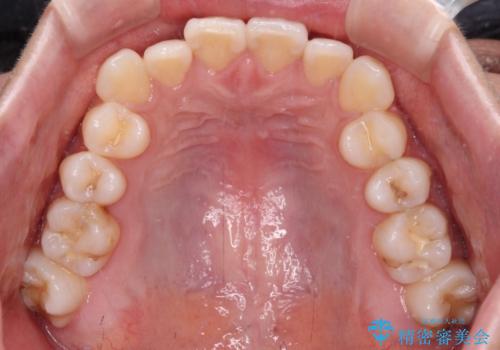

- 前歯のデコボコと奥歯の咬み合わせを気にして来院された患者様です。

右側の奥歯は、上が外側に転位した鋏状咬合を呈しており、前歯のデコボコ改善と並行して咬み合わせを改善していく必要がありました。